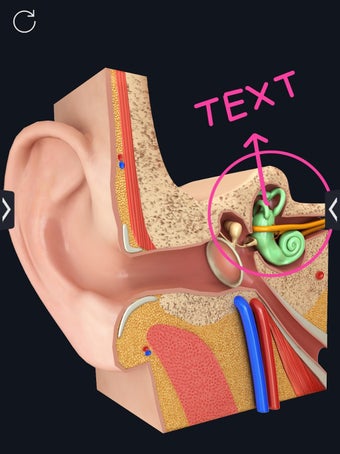

My Organs Anatomy es una aplicación de anatomía 3D gratuita desarrollada por Visual 3D Science para usuarios de Android. Esta aplicación proporciona un modelo 3D altamente realista de los órganos humanos que se puede girar 360°, acercar y alejar, y ver desde cualquier ángulo. La aplicación está diseñada para proporcionar una mirada detallada a la anatomía de los órganos humanos y ofrece varias características para ayudar a los usuarios a explorar y aprender.

La interfaz fácil de usar de My Organs Anatomy permite una navegación sencilla, lo que facilita la selección, rayos X, ocultación y visualización de órganos individuales. La aplicación también incluye un modo de animación, opciones de búsqueda y un panel de información que proporciona información relacionada. Además, la aplicación ofrece pronunciación de audio para todos los términos anatómicos, e incluso los usuarios pueden dibujar o escribir en la pantalla y compartir capturas de pantalla.